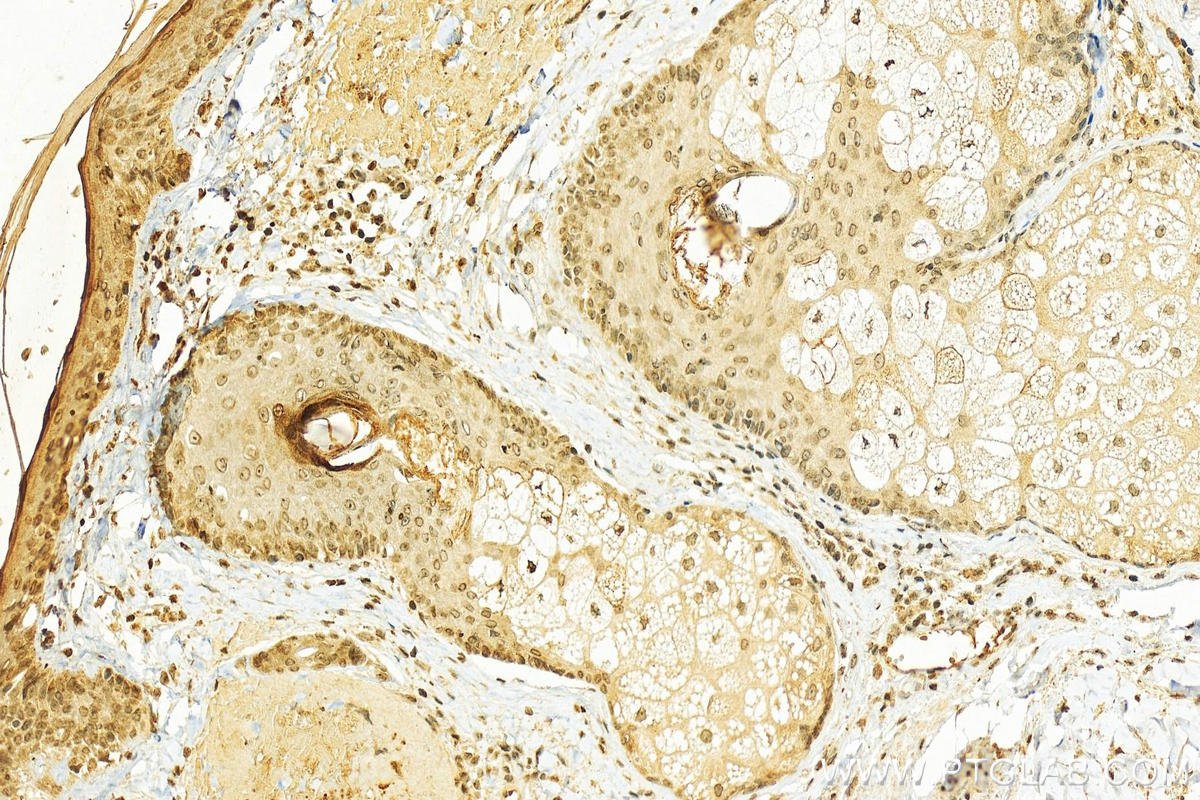

| Positive IHC detected in | rat skin tissue, human paracancerous, human paracancerous tissue of skin, mouse skin tissue Note: suggested antigen retrieval with TE buffer pH 9.0; (*) Alternatively, antigen retrieval may be performed with citrate buffer pH 6.0 |

Loricrin, also named LOR and LRN, is a major component of the cornified cell envelope (CE) expressed late in epidermal differentiation in the granular layers of normal skin. This antibody is specific to Loricrin.